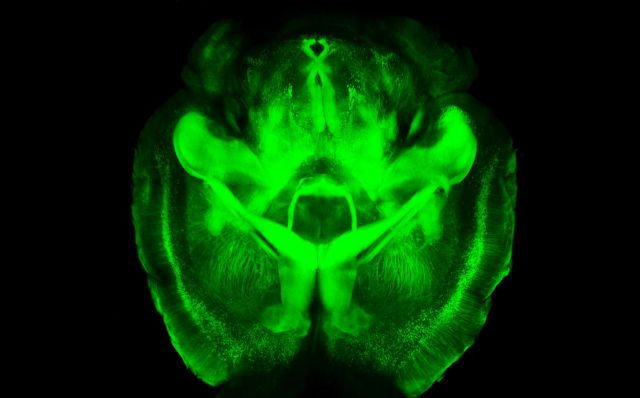

Η τεχνική που ανέπτυξαν οι επιστήμονες του Στάνφορντ με επικεφαλής τον ψυχίατρο και ειδικό στην εμβιομηχανική Καρλ Ντάισεροτ καθιστά τα όργανα διαπερατά από το φως – δηλαδή διάφανα – διατηρώντας όμως παράλληλα ανέπαφη την ανατομική και μοριακή δομή τους. Η CLARITY όπως την ονομάζουν (Clear Lipid-exchanged Acrylamide-hybridized Rigid Imaging/Immunostaining/In situ hybridization-compatible Tissue-hYdrogel) εφαρμόστηκε πειραματικά για να αποκαλύψει με πρωτοφανή λεπτομέρεια τη νευρολογική δικτύωση του εγκεφάλου ενός ποντικού, πραγματοποιώντας ένα μεγάλο άλμα στην ιατρική απεικόνιση.

Αριστερά ο εγκέφαλος ενός ποντικού και δεξιά η διάφανη εκδοχή του με την εφαρμογή της CLARITY με φόντο μια φράση του διάσημου νευροεπιστήμονα Σαντιάγο Ραμόν ι Καχάλ (Πηγή Kwanghun Chung and Karl Deisseroth, Howard Hughes Medical Institute/Stanford University)

Όπως περιγράφεται στη σχετική δημοσίευση στην επιθεώρηση «Nature», η νέα μέθοδος βασίζεται στη χρήση μιας ειδικής διάφανης υδρογέλης. Αρχικά οι επιστήμονες αφαίρεσαν τον εγκέφαλο ενός ποντικού και ενέχυσαν σε αυτόν τη διάφανη υδρογέλη η οποία συγκεντρώνεται στις λιπώδεις μεμβράνες των νευρώνων (οι λιπώδεις μεμβράνες που περιβάλλουν τα κύτταρα αποτελούν ένα βασικό εμπόδιο στην προσπάθεια των ειδικών να «δούν» μέσα στα όργανα).

Καθώς η υδρογέλη στερεοποιήθηκε πήρε το σχήμα των μεμβρανών δημιουργώντας μια μήτρα η οποία συγκράτησε στη θέση τους τις πρωτεΐνες, το DNA και το RNA των κυττάρων. Στη συνέχεια οι επιστήμονες ενέχυσαν ένα χημικό το οποίο διέλυσε τις λιπώδεις μεμβράνες δημιουργώντας έναν διάφανο εγκέφαλο από ζελέ στον οποίο όλο το μοριακό υλικό (πρωτεΐνες, RNA και DNA) βρίσκεται ανέπαφο στην αρχική του θέση ενώ παράλληλα διακρίνονται λεπτομερώς τόσο η δομή των μεμονωμένων νευρώνων όσο και οι συνδέσεις μεταξύ τους.

Η θέση του μοριακού υλικού καθίσταται ορατή εγχέοντας φθορίζοντες δείκτες – κάτι το οποίο, όπως τονίζουν οι ειδικοί, μπορεί να βοηθήσει στο να ανιχνευθεί ποια γονίδια εκφράζονται στα μεμονωμένα κύτταρα αποκαλύπτοντας τη λειτουργία που αυτά επιτελούν μέσα στον εγκέφαλο.